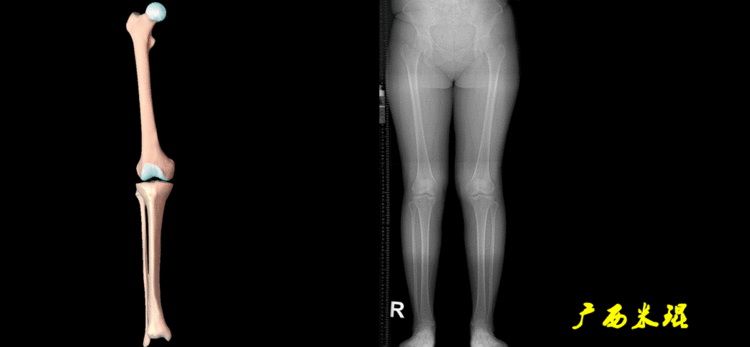

四、下肢全长片测量的意义

1、判定有无畸形下肢的畸形定义为生理轴线的偏移。关节角和轴线在冠状面、矢状面和横断面上可发生病理改变,并引起整个下肢的对线异常。

最常见的下肢畸形发生于冠状面,即膝内外翻畸形,冠状面的对线异常通过应用“对线异常检验”进行分析,机械轴的偏移(MAD)表现为对线异常。

膝内翻是指下肢力线通过膝关节中心点内侧,距中点2mm以上,偏内超过15mm为显著膝内翻。膝外翻是指下肢力线通过膝关节中心点外侧,距中点2mm以上,偏外超过10mm为显著膝外翻。

2、判断畸形的部位画出下肢全长片中的机械轴和力线轴,确定畸形来自股骨、胫骨还是关节内。首先我们确认股骨机械轴及mLDFA,超出范围为股骨畸形;然后我们确认胫骨机械轴及MPTA,超出范围为胫骨畸形;最后我们确认关节线的汇聚关系JLCA,超出范围为关节内畸形。

总之,下肢力线及相关角度测量是我们骨科医生的基本功,我们必须想尽办法学会它及使用它。本文作者米琨老师!